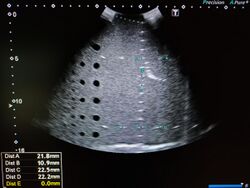

Imaging phantom as seen on a medical ultrasound machine.

A phantom used to evaluate an imaging device should respond in a similar manner to how human tissues and organs would act in that specific imaging modality. For instance, phantoms made for 2D radiography may hold various quantities of x-ray contrast agents with similar x-ray absorbing properties (such as the attenuation coefficient) to normal tissue to tune the contrast of the imaging device or modulate the patient's exposure to radiation. In such a case, the radiography phantom would not necessarily need to have similar textures and mechanical properties since these are not relevant in x-ray imaging modalities. However, in the case of ultrasonography, a phantom with similar rheological and ultrasound scattering properties to real tissue would be essential, but x-ray absorbing properties would not be relevant.[2]